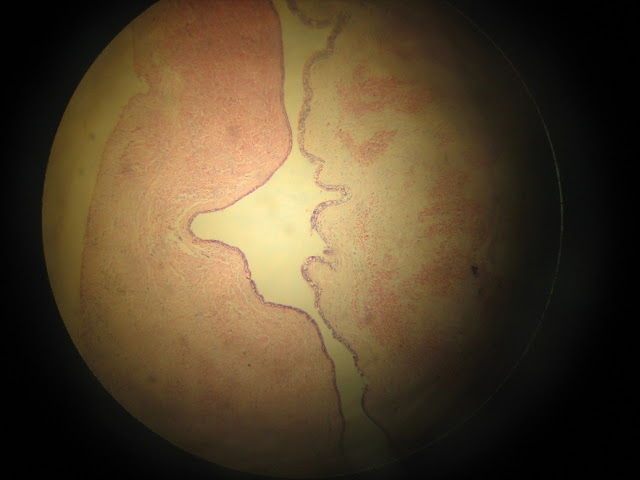

Typycal Histological features of odontogenic keratocyst

• Epithelial lining of uniform thickness

• Flat lower border of epithelium

• Clearly defined basal layer of tall cells in parakeratinized cysts

• Thin eosinophilic layer of para keratin

• Cyst lining typically much folded

• Epithelial lining weakly attached to the fibrous wall

• Thin fibrous wall

• Satellite cysts in the wall

• Inflammatory cells typically absent or scanty